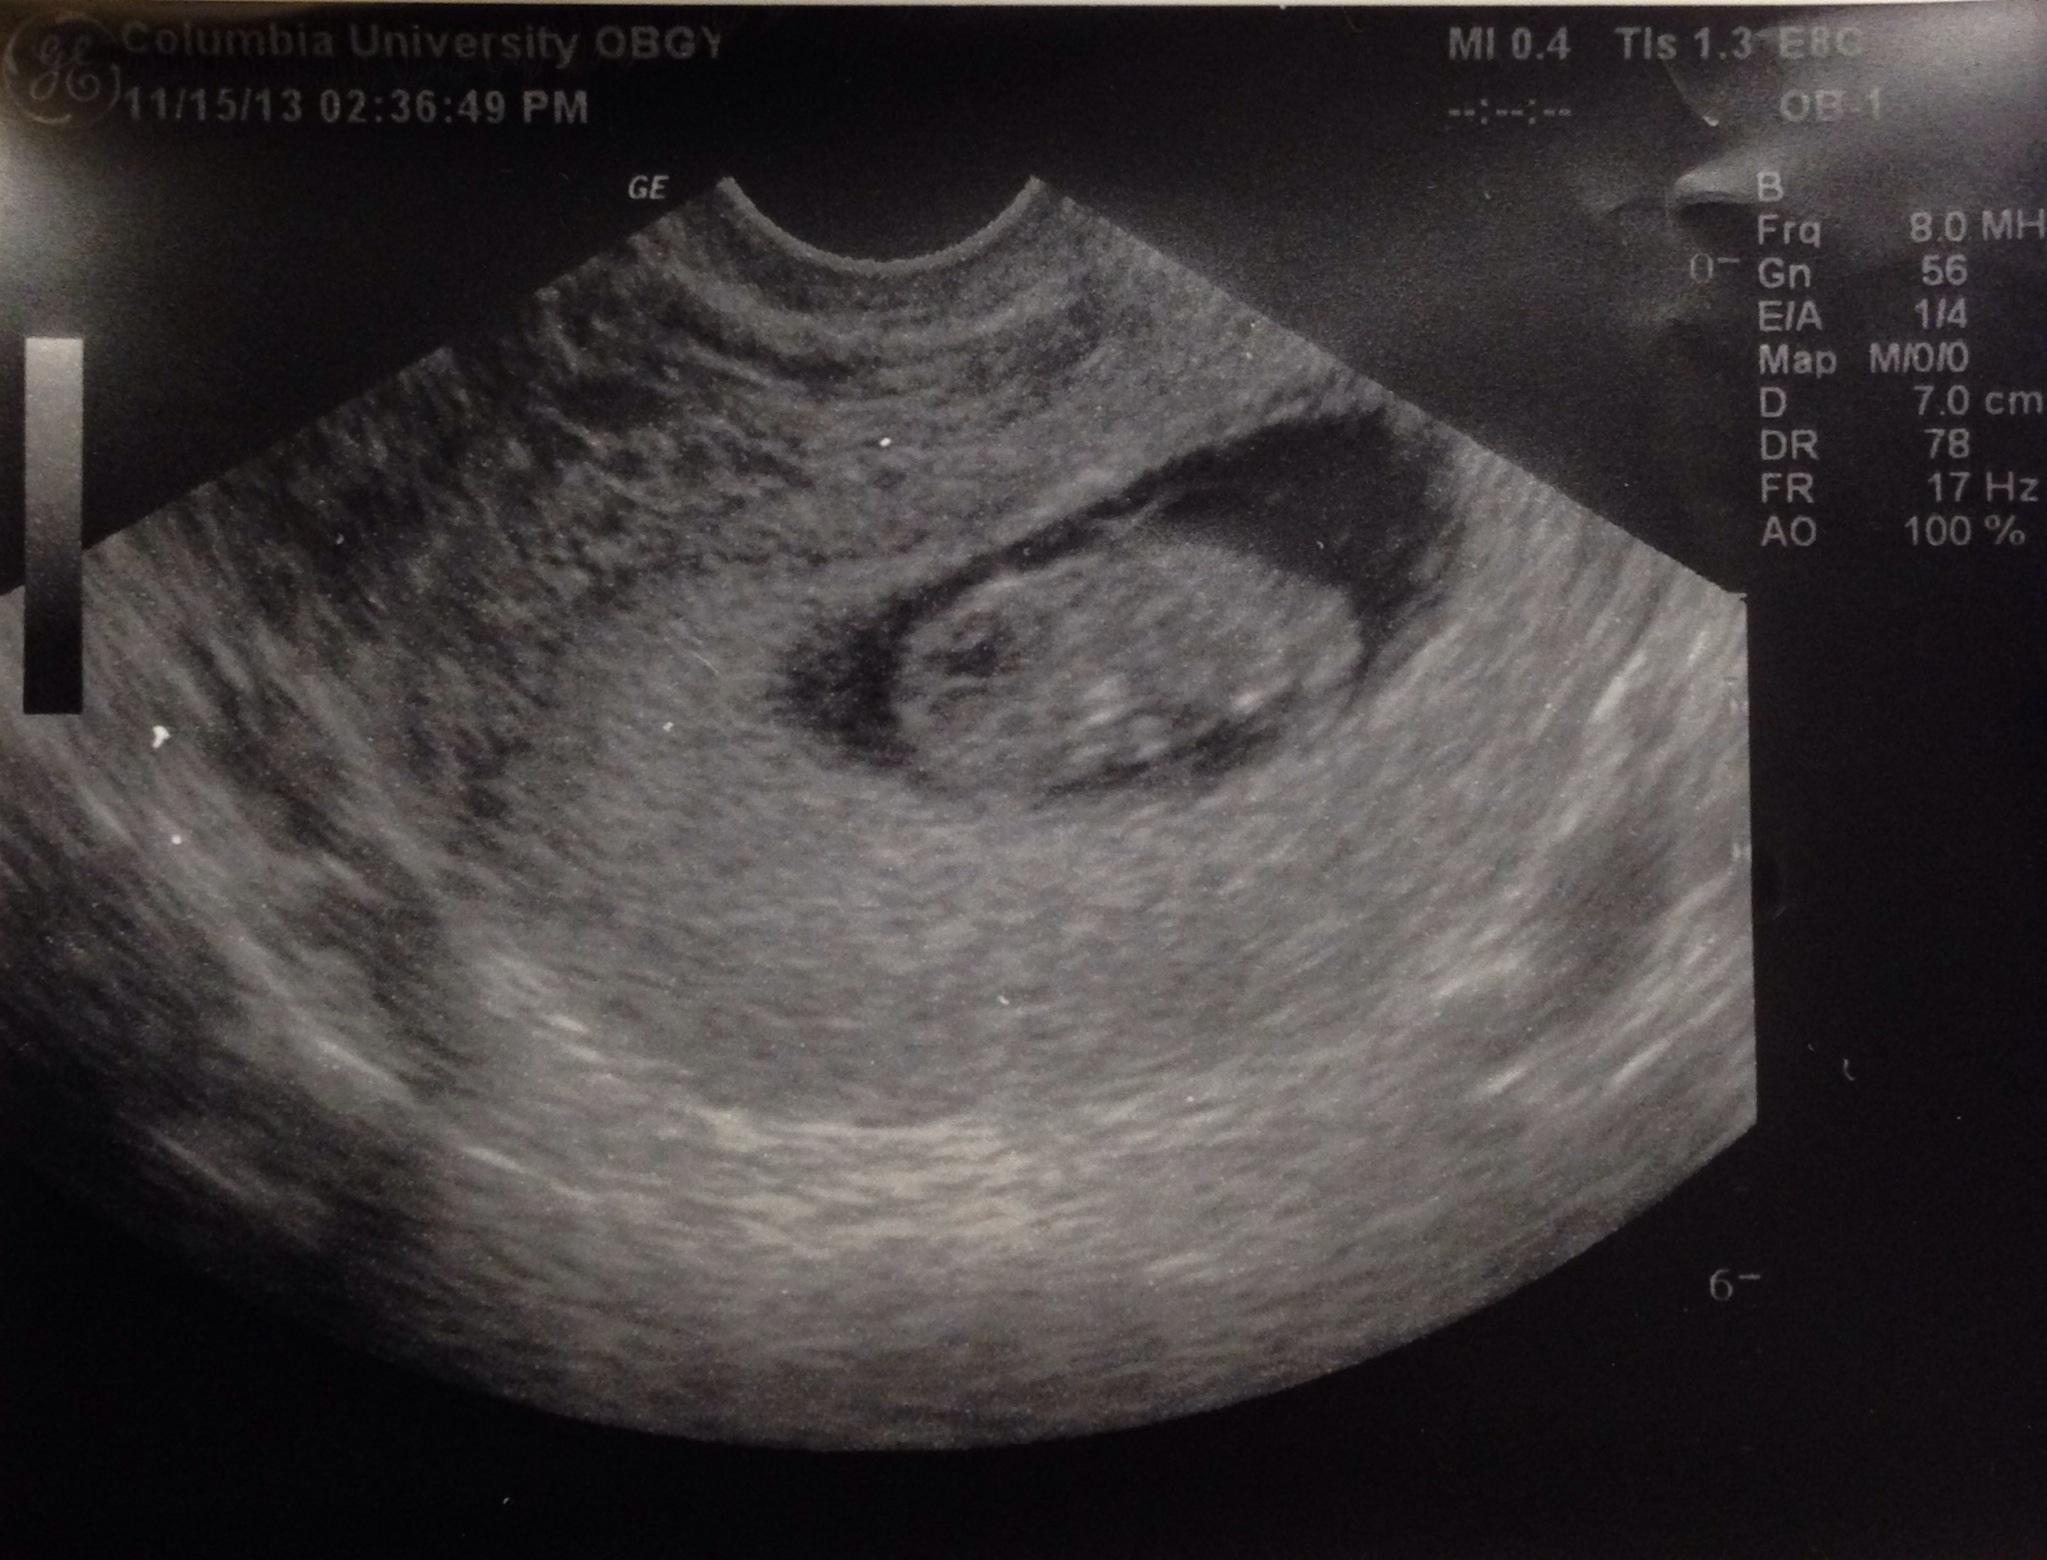

10/17: U/S shows healthy bean @ 6w6d, HR 119 10/25: U/S shows bean is growing @ 8w0d, HR 158!

@allytales - there's totally a baby in there!!!